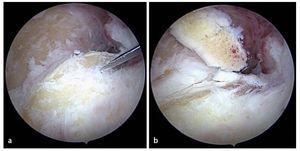

Fig. 11 a, b) Los osteofitos en la zona del proceso coronario se extraen con un cincel Lambotte. c) Los fragmentos osteocondriales se extraen de la articulación con una pinza de agarre. d) El proceso coronoides remanente se alisa con el resector sinovial o una fresa de bola (no representado en la imagen).

Fig. 12 Las formaciones osteofíticas del borde del húmero anterior se pueden extraer progresivamente con una fresa de bola.

Fig. 13 Para finalizar, se verifica la amplitud de movimiento del codo. En caso de déficit en flexión remanente se puede realizar una liberación capsular en el compartimento anterior bajo control artroscópico. La cápsula se separa con precaución de sus inserciones en el húmero distal mediante el resector sinovial. Como alternativa se puede utilizar también un raspador.

Fig. 14 La artroscopia en el compartimento posterior se inicia con la realización del abordaje dorsorradial y del abordaje transtendinoso desde el cual se introducirán los instrumentos (Figs. 6c). En el ángulo visual de la cámara por encima del portal posteroradial se encuentran la punta del olécranon y la fosa olecraniana. a) Con frecuencia existen adherencias masivas en la zona de la fosa olecraniana, que se separan con un resector sinovial y se extraen. b) En los casos con graves limitaciones de movimiento se puede realizar también una cirugía de la fosa con una fresa para hueso (no se representa en la imagen). Mediante esta cirugía se extraen las formaciones óseas molestas, así como formaciones osteofíticas en la zona de la fosa olecraniana, hasta que se restituye la libre movilidad entre el olécranon y la fosa olecraniana.